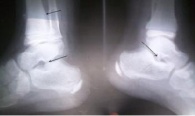

La imagen radiológica de las exostosis se caracteriza por mostrar una proliferación ósea compacta con estructura esponjosa en su interior; las exostosis pueden ser sésiles o pediculadas. Su cuerpo puede tomar una dirección más o menos paralela a la diáfisis o perpendicular a esta, y su porción Terminal puede ser redondeada, puntiaguda, en forma de hongo o de coliflor.